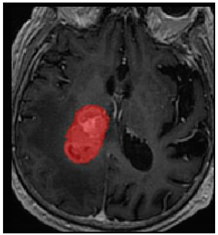

Three cases from the NTUH dataset showing representative results of different models were shown in Table 2, Table 3 and Table 4. The overall dice scores of these networks on the NTUH dataset ranged from 0.33 (DeepMedic) to 0.51 (V-Net). Table 5 shows the detailed performance of each network tested with the NTUH dataset.

Table 4. Predictions with high dice scores.

Ground truthDeconvNetDeepMedic

Applsci 11 09180 i013 Applsci 11 09180 i014 Applsci 11 09180 i015

PSPNetU-NetV-Net

Applsci 11 09180 i016 Applsci 11 09180 i017 Applsci 11 09180 i018